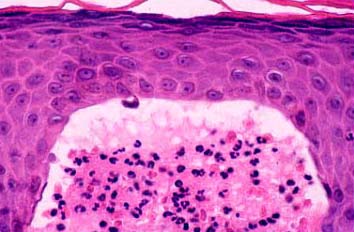

. The typical histologic features are best observed in erythematous skin adjacent to early blisters. In these zones, neutrophils accumulate at the tips of dermal papillae. With an increase in size to microabscesses, a significant admixture of eosinophils may be noted. As microabscesses form, a separation develops between the tips of the dermal papillae and the overlying epidermis; thus, the early blisters are multiloculated . The presence of fibrin in the papillae may give them a bluish appearance. Within 1 to 2 days, the rete ridges lose their attachment to the dermis, and the blisters then become unilocular  and clinically apparent. At this time, the characteristic papillary microabscesses may be observed at the blister periphery. For this reason, the inclusion of perivesicular skin in the biopsy specimen is of

utmost value. The papillary dermis beneath the papillae may have a relatively intense inflammatory infiltrate of neutrophils and some eosinophils. Many neutrophils may exhibit leukocytoclasis. Subjacent to this, a perivascular infiltrate composed of lymphocytes, neutrophils, and eosinophils may be apparent. the diagnostic finding of papillary microabscesses may not be present in all patients. Apoptotic keratinocytes may be noted above the papillary microabscesses.